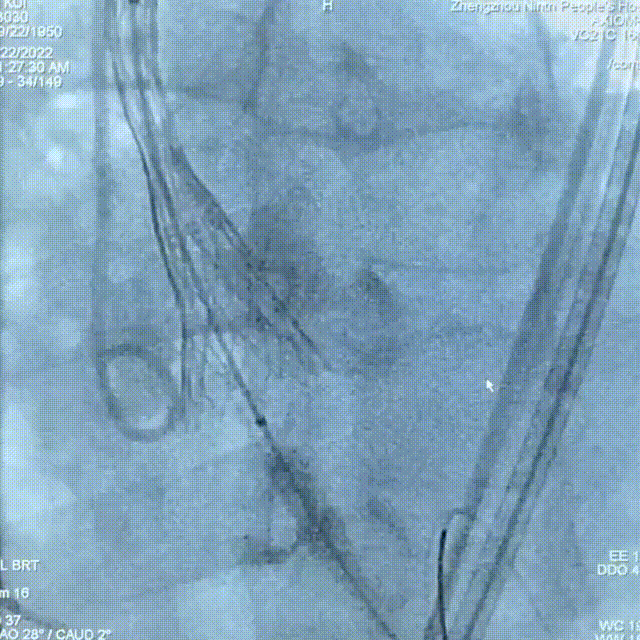

术后造影

术中患者生命体征平稳,手术顺利完成。术后心超提示,释放后人工瓣膜正常工作,主动脉瓣跨瓣压差由术前的96mmHg改善至术后的0mmHg,主动脉瓣口前向血流速度由术前的4.9m/s改善至术后的1.9m/s,患者血流动力学得到明显改善。术前患者步行30米即感胸闷、呼吸困难,术后步行实验显示患者步行380米亦无任何不适,可见患者生存质量得到明显提高。